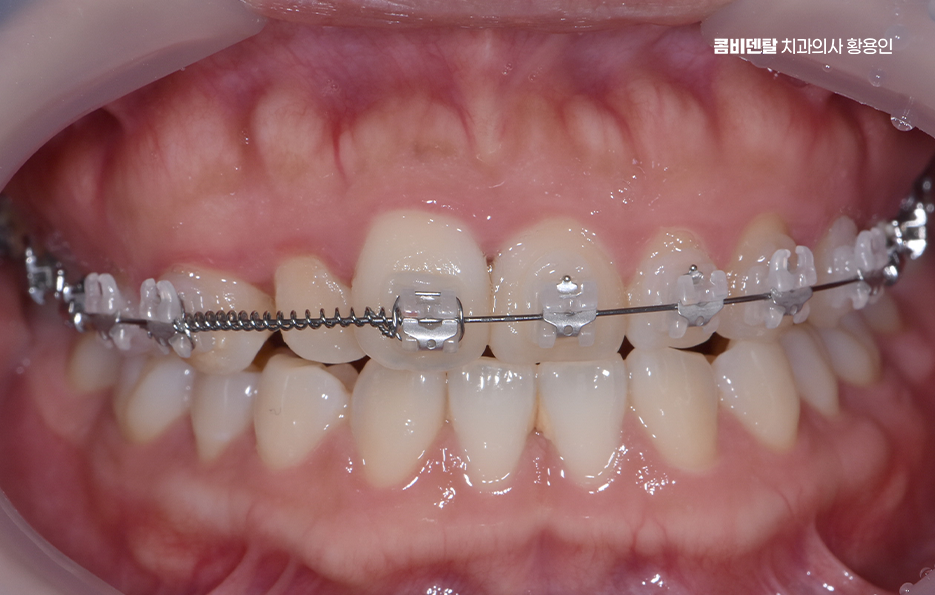

교정 장치의 종류에 따라서도 통증의 정도가 다를 수 있는데 일반적인 금속 브라켓을 사용하는 경우, 초기에는 금속이 입 안쪽에 닿으면서 불편함을 느낄 수 있어요. 특히 교정 와이어를 조절할 때마다 일정한 힘이 가해지기 때문에 몇 일 동안은 씹는 것이 불편할 수도 있지만 반면, 클리피씨 같은 자가 결찰형 브라켓을 사용하는 경우, 마찰력이 줄어들면서 치아 이동 속도가 상대적으로 빠르고, 통증이 덜하다고 느낄 수 있어요. 또한 투명 교정이나 인비절라인 같은 경우에는 탈착이 가능하고 교정기로 인한 통증이 일반교정에 비해 상대적으로 덜한 편이라는 특징이 있어요